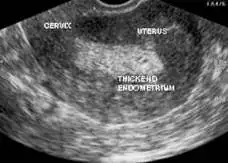

Evet rahim duvarıyla ilgili 3 çizgi sağ sol duvarın eşit ve belirgin şekilde oluşmasıyla oluyor geçen resim paylaşmıştım.zaman zaman olabiliyor kalıcı bir durum değil 3 çizgi olmaması .östrojen dağılımıyla ilgiliKızlar merhabalar son günlerde 3 çizgi olayını görür oldum bu sayfalarda. Rahim kalınlığıyla mı ilgili bu ilk kez duydum?

Yarın bakayım bakalım benımkı nasıl gorunecek1.resim dalgalı yani eşit şekilde kalınlaşmamıs bir tarafı ince bir tarafı kalın

2.3.çizgi oluşmamış fazla kalın rahim duvarı

3.3çizgi oluşmuş transfere uygun duvar

Evet malesef ben acı bı sekilde tanıştım hep okudum öncesinde kalınlık yüzünden iptal onu takmıştım bende ama onda bile bı sistem varmış1.resim dalgalı yani eşit şekilde kalınlaşmamıs bir tarafı ince bir tarafı kalın

Ben de gittim bugün kontrole çok şükür 10.4 dedi doktor çatlatma iğnemi oldum hormonlar da iyi çıktı haftaya salı transferim var inşallahSelam kızlar

Kontrole gıttım bugun estrofemın 6.günü bugun endometrıum 9.2, doktor cok guzel dedı hatta Hemsıreye emın mısın 6.gun oldugunda dedı, sonra ılac dozunu düşürdüler, bir gün sabah aksam, diğer gün sabah ikindi gece, çarşambaya kadar boyle olacak.. Kontrol çarşamaba gunu